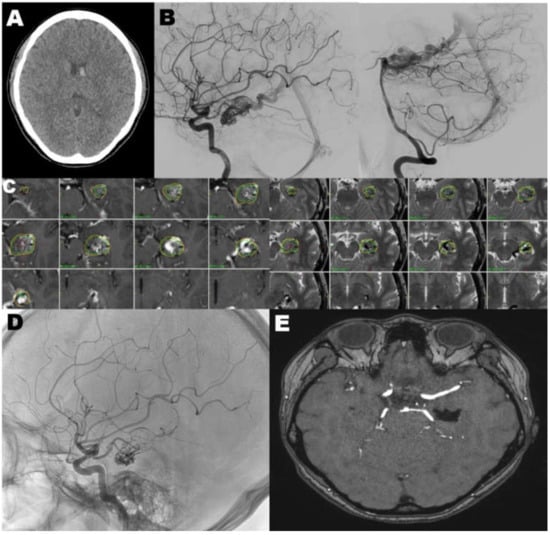

4.2. Case 2